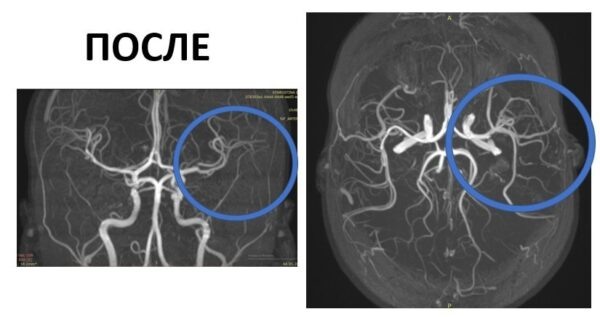

Как рассказала заведующая отделением неврологии Нина Маслова, тяжелое состояние могло привести к непредсказуемым последствиям, в том числе к смерти. «Если такой пациент попадает в больницу в первые 4,5 часа после появления симптомов, есть возможность быстро восстановить кровоток. К счастью, благодаря оперативности родителей и слаженной работе команды, девочка была доставлена через два часа после появления симптомов. Мы успели провести тромболизис – медикаментозную процедуру растворения тромба. Это спасло ребенка от тяжелой инвалидности или даже смерти», – рассказала завотделением неврологии Нина Маслова.

Фото: Детский центр им. Рошаля. vk.com

«Сейчас состояние девочки стабильное, она проходит восстановительную терапию в больнице. В будущем ее ждет лечебный курс, который ее ждет в отделении медицинской реабилитации», – добавила врач.